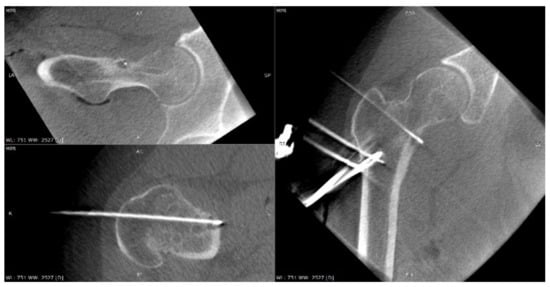

3.4. Case 4: OO Masking as a Fatigue Fracture